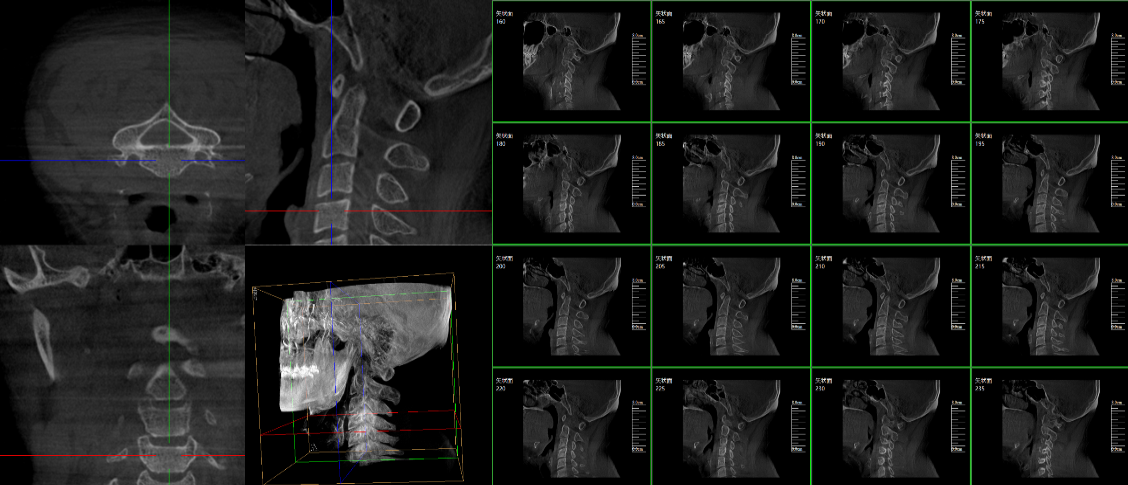

現(xiàn)在很多廠家或者經(jīng)銷商都在推廣三維c型臂,那么,三維c型臂是什么意思?三維c型臂是一款新型C形臂,實(shí)現(xiàn)了術(shù)中影像從二維到三維的飛躍。通過不同方位的斷層圖像,能夠更清晰、完整地顯示椎體及其附件的解剖學(xué)結(jié)果,直觀地分析病變與周圍組織的立體空間關(guān)系,三維斷層成像能夠使手術(shù)模擬和手術(shù)方案的制定更加準(zhǔn)確。

脊柱外科的應(yīng)用:有研究表明,在三維c型臂圖像引導(dǎo)的下頸椎或胸椎后路螺釘置入術(shù)中,螺釘正確置入率可達(dá)92.7%,在三維c型臂圖像引導(dǎo)的椎間孔腰椎椎間盤融合術(shù)中,術(shù)者被輻射總量明顯降低。此外三維c型臂可以搭配骨科手術(shù)導(dǎo)航和機(jī)器人使用,能將該過程智能化和準(zhǔn)確化,進(jìn)一步提高螺釘?shù)闹踩肼省?/span>

創(chuàng)傷外科的應(yīng)用:由于創(chuàng)傷外科的患者多數(shù)為急、重癥患者,以致術(shù)前準(zhǔn)備時(shí)間較短,很多都需行急診手術(shù),三維c型臂可以在術(shù)中實(shí)時(shí)重建三維圖像,使手術(shù)醫(yī)生對(duì)一些復(fù)雜骨折更加充分的了解,并且能夠在術(shù)中即時(shí)校正螺釘?shù)奈恢茫泳_地置入固定器材,減少術(shù)中及術(shù)后發(fā)生并發(fā)癥的幾率,極大限度地縮短螺釘置入時(shí)間。